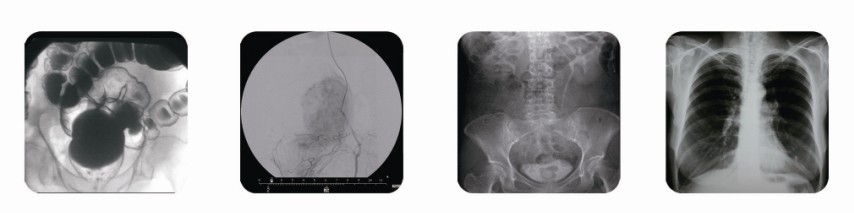

隨著我國近年醫(yī)學影像數(shù)字化發(fā)展,遙控胃腸x光機的發(fā)展也慢慢從模擬向數(shù)字化方向發(fā)展。遙控胃腸x光機傳統(tǒng)的胃腸x光機更加方便快捷,在整個檢查中,病人的信息可通過數(shù)字化存貯、回放、成像,極大提高病變診斷的準確性遙控胃腸x光機給醫(yī)院帶來了極高的效益

目前,用高科技術(shù)生產(chǎn)遙控胃腸x光機的廠家在國內(nèi)并不多見,雖然有些廠家生產(chǎn)出來的胃腸x光機成像還不錯,但是產(chǎn)品在技術(shù)上還是不及南京地區(qū)的某些廠家的產(chǎn)品,像南京地區(qū)的普朗醫(yī)用設備有限公司生產(chǎn)的遙控胃腸x光機,普朗醫(yī)療生產(chǎn)的遙控胃腸x光機應用數(shù)字透視,多方位觀察器官病變,并可保留末幀圖像,圖像清晰。該設備既可使用IP板完成計算機X線數(shù)字攝影,直接使用數(shù)字攝影,大大提高拍片質(zhì)量。且該設備在臨床上還有很多用途,顯著提高了醫(yī)生的工作效率。是國內(nèi)外醫(yī)院及相關(guān)部門的首選品牌。

點擊下圖中紅色產(chǎn)品名稱可查看該產(chǎn)品詳細特點介紹,另外,您也可以點擊頁面上的“點我咨詢”對話框咨詢血紅蛋白儀酶標儀、X光機、食品安全檢測儀等產(chǎn)品信息。

(普朗醫(yī)療品牌——高頻醫(yī)用診斷X射線機PLD6000遙控胃腸x光機))